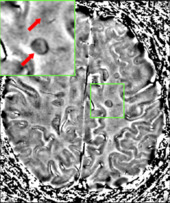

Blood–brain barrier

The blood–brain barrier (BBB) is a part of the capillary system that prevents the entry of T cells into the central nervous system. It may become permeable to these types of cells secondary to an infection by a virus or bacteria. After it repairs itself, typically once the infection has cleared, T cells may remain trapped inside the brain.[8] Gadolinium cannot cross a normal BBB and, therefore, gadolinium-enhanced MRI is used to show BBB breakdowns.[51]

Clinical data alone may be sufficient for a diagnosis of MS if an individual has had separate episodes of neurological symptoms characteristic of the disease.[54] In those who seek medical attention after only one attack, other testing is needed for the diagnosis. The most commonly used diagnostic tools are neuroimaging, analysis of cerebrospinal fluid and evoked potentials. Magnetic resonance imaging of the brain and spine may show areas of demyelination (lesions or plaques). Gadolinium can be administered intravenously as a contrast agent to highlight active plaques and, by elimination, demonstrate the existence of historical lesions not associated with symptoms at the moment of the evaluation.[54][55] Testing of cerebrospinal fluid obtained from a lumbar puncture can provide evidence of chronic inflammation in the central nervous system. The cerebrospinal fluid is tested for oligoclonal bands of IgG on electrophoresis, which are inflammation markers found in 75–85% of people with MS.[54][56] The nervous system in MS may respond less actively to stimulation of the optic nerve and sensory nerves due to demyelination of such pathways. These brain responses can be examined using visual- and sensory-evoked potentials.[57]